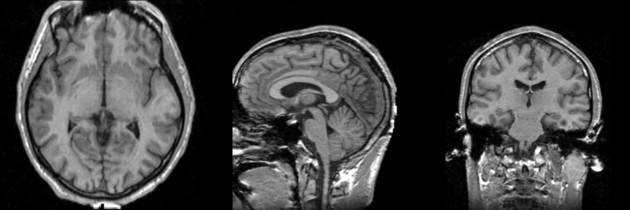

| Template (T1) | CSF | GM | WM |